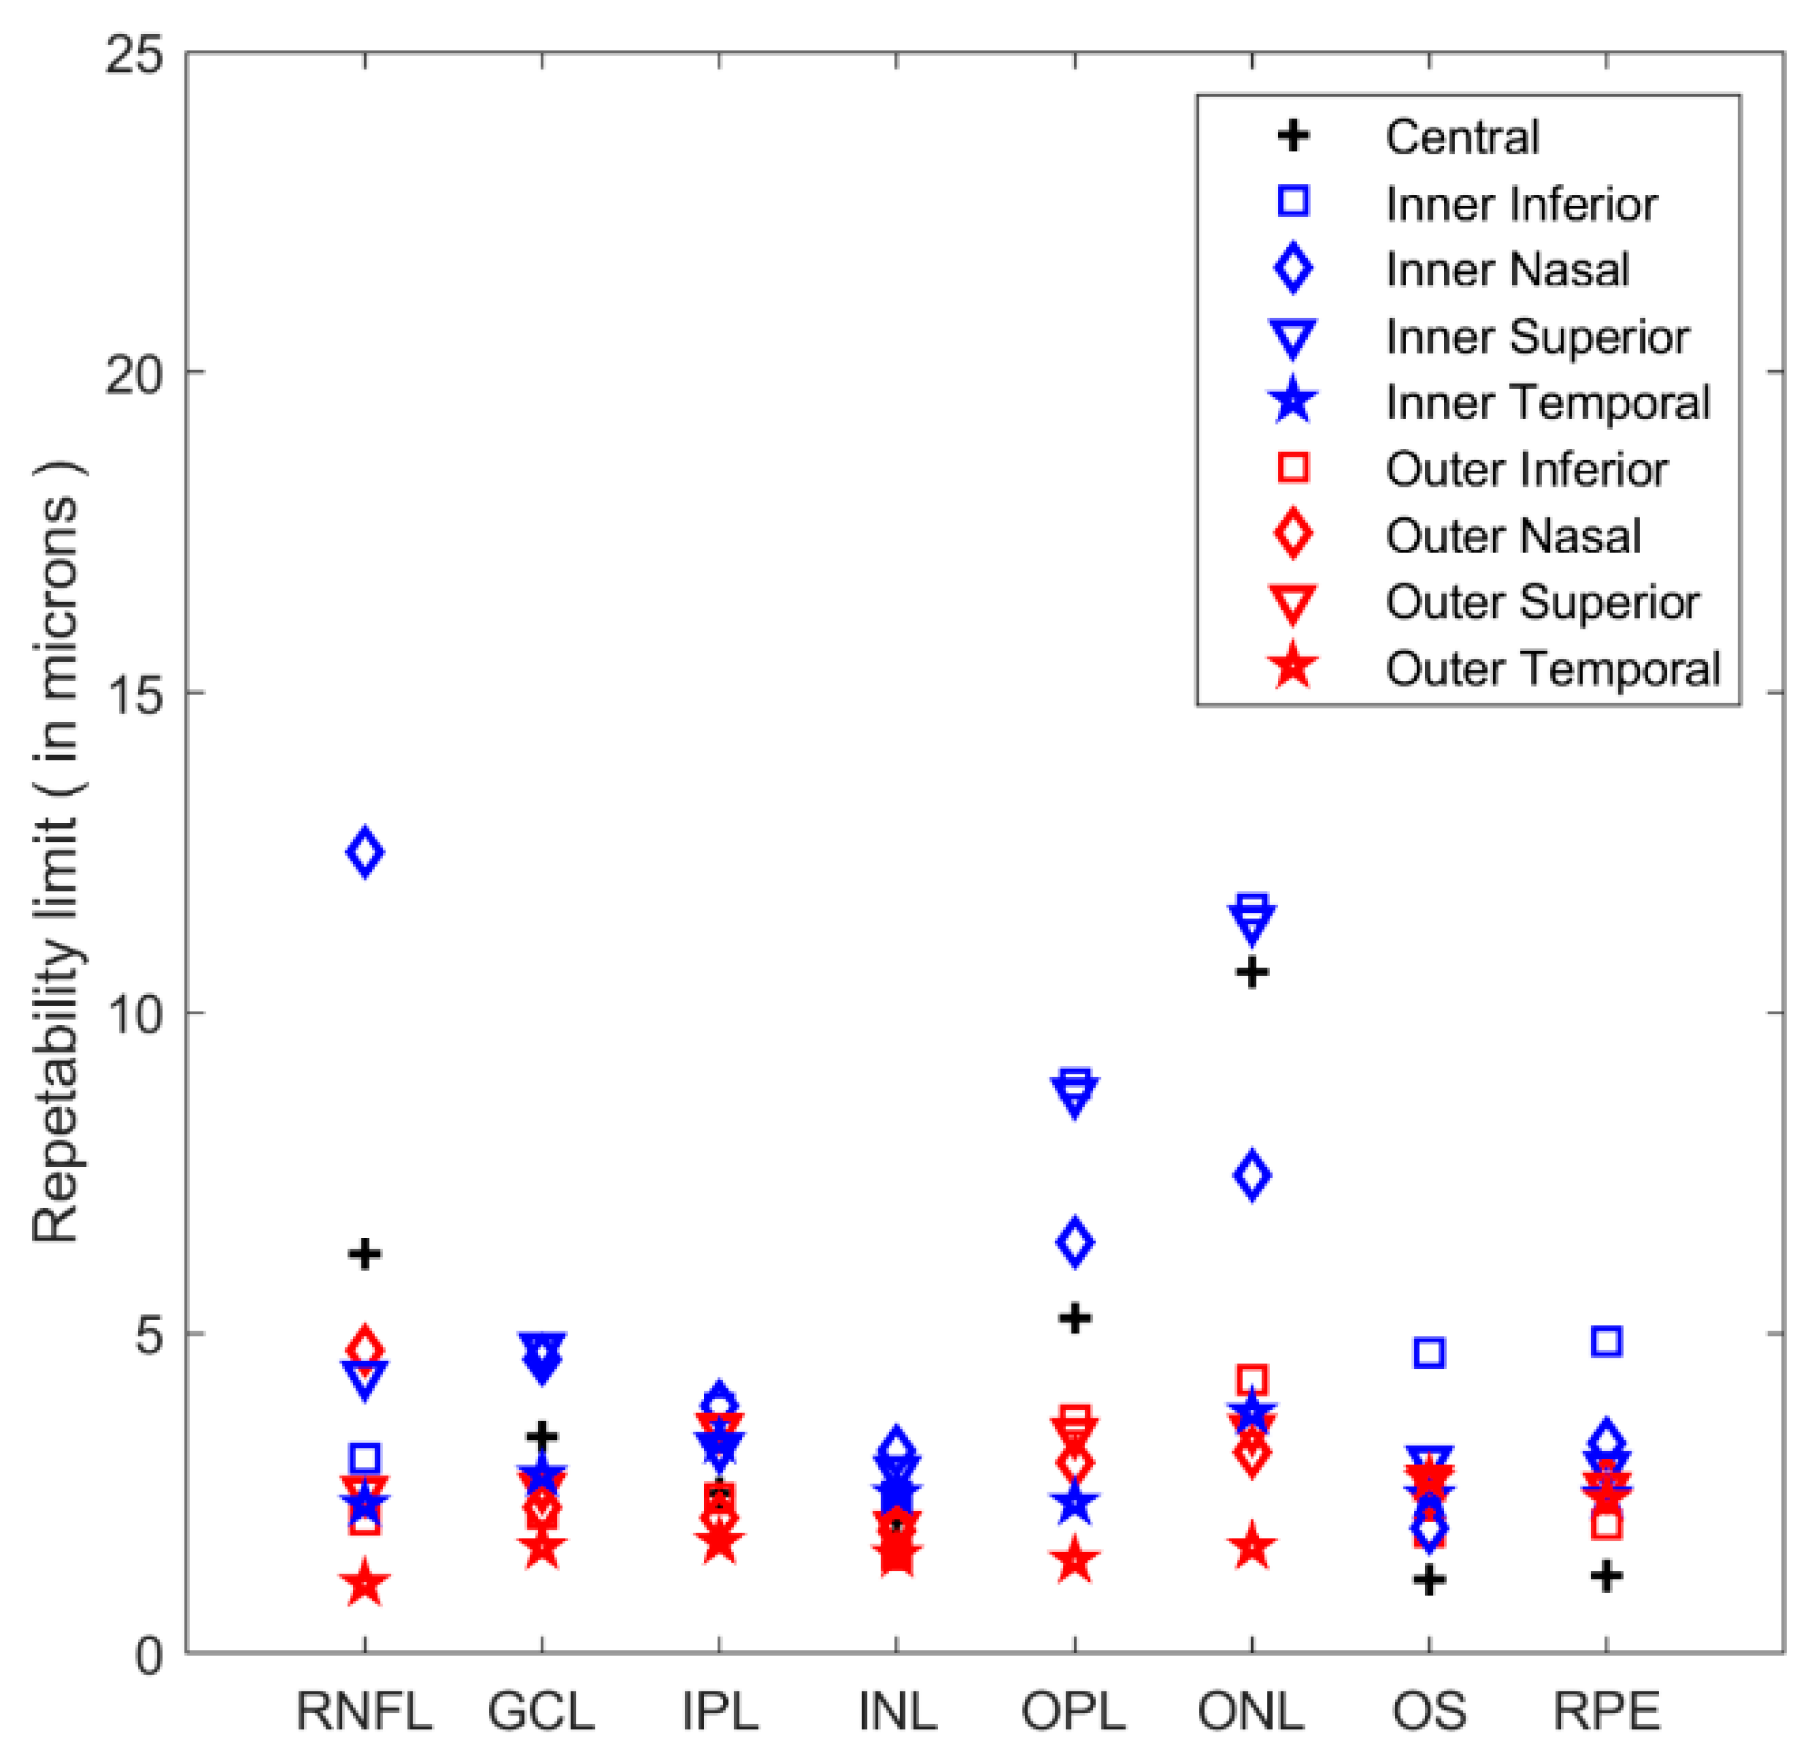

3. Results